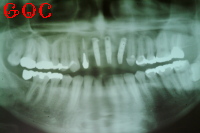

▼インプラント後![]() |

その手術が終わり半年後くらいして落ち着いた段階で、上顎前歯に3本のインプラントを埋め込みました。

インプラントにしてたいへん満足しています。

噛んだ感触も自分の歯と変わらないほどです。

外観についてもこれ以上望めないほど、修復されたと思います。

家族や友人からは"天然の歯とまったく区別がつかない"と言われます。